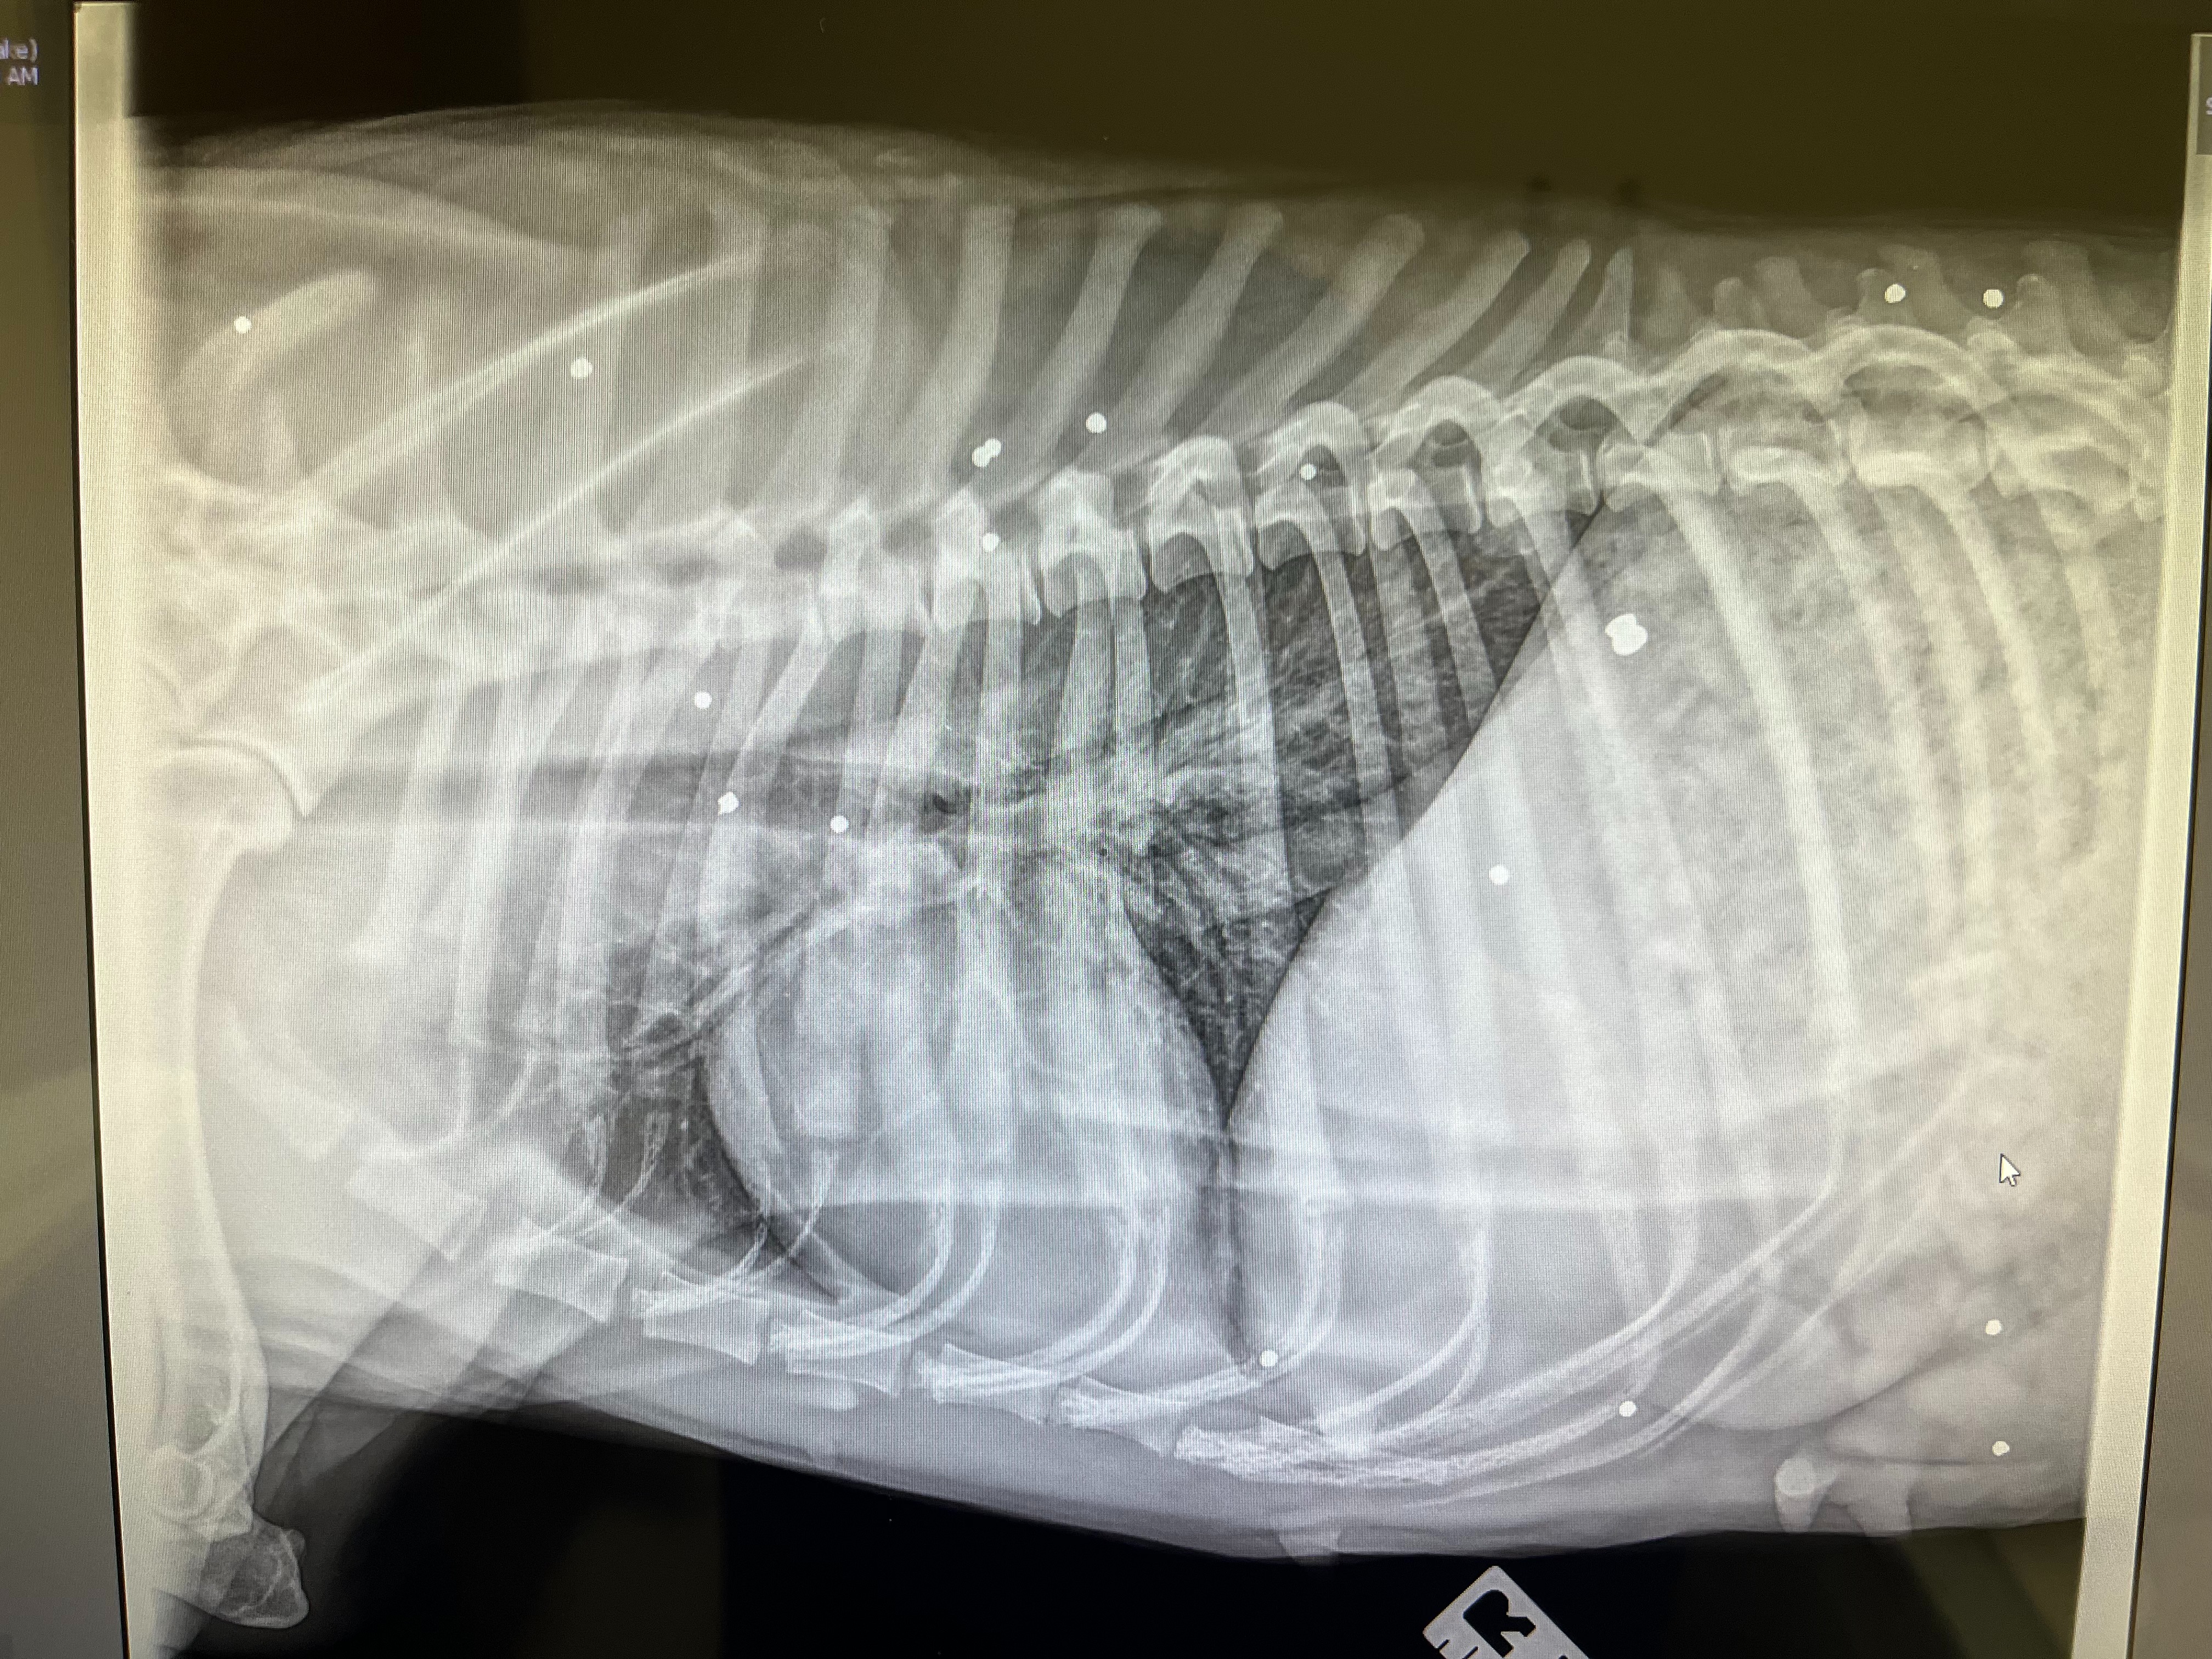

With the help of Dr. Andrew Atuan, a local Atlanta vet, we were able to get them cleaned up, medicated, and stabilized. But as the days passed, it became clear that Roxy wasn’t healing—she struggled to walk and carried a painful limp. X-rays revealed the heartbreaking truth: her femur is completely broken, and she carries the scars of multiple gunshot wounds. It is nothing short of a miracle that she is alive and even more incredible that, through it all, she never stopped protecting and caring for her puppy, Milo.